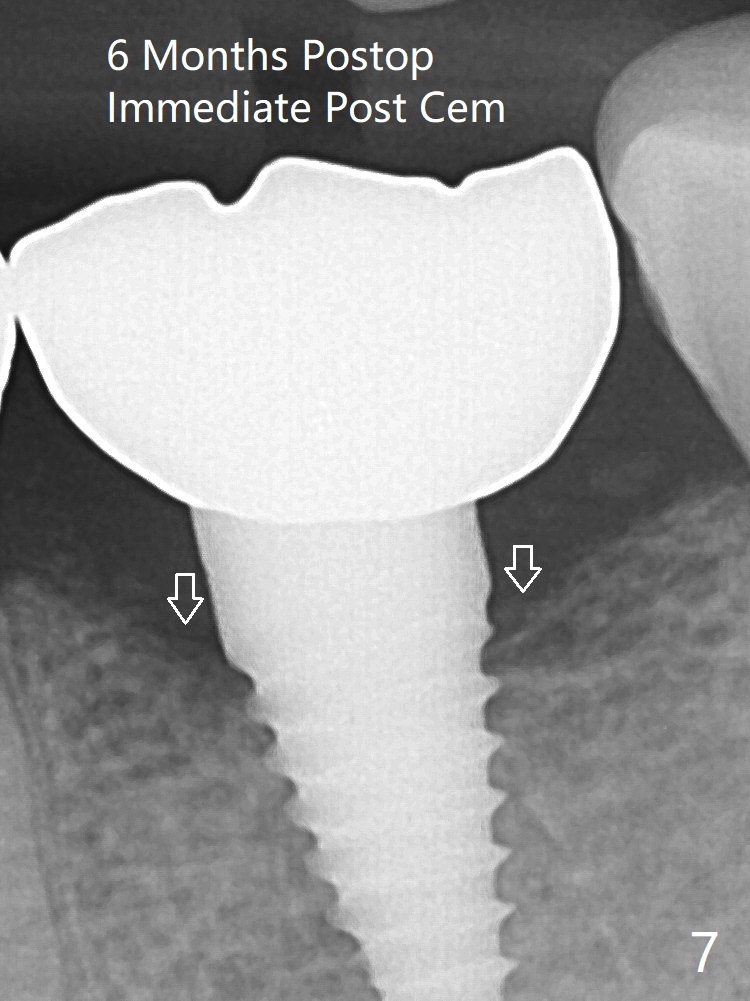

病人抱怨用临时牙冠咀嚼疼痛,不咬后没有不舒服,其实临时牙冠咬合面穿孔,牙龈正常,永久粘固剂没有外溢(图七)。术后4.5-6个月植体周围骨质吸收(图六,七:箭头)。牙槽嵴处钻洞应与植体直径一样才能减少骨质吸收。